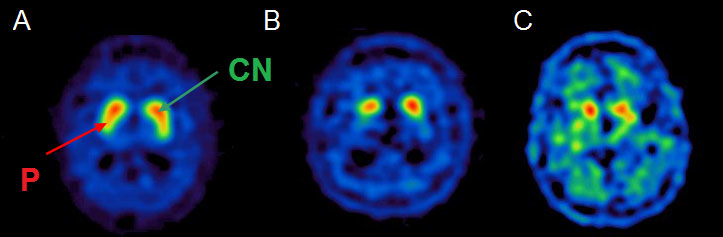

Due to the widespread availability of SPECT scans and approval from European (since 2000) and US (since 2011) medical agencies in the evaluation of parkinsonian syndromes, 123I-FP-CIT SPECT has been the most studied molecular imaging technique in degenerative parkinsonian syndromes [27]. There is satisfactory medical evidence that it can distinguish Parkinson’s disease from essential tremor (class I) [28] and drug-induced parkinsonism (class II) [29]. It is indicated for distinguishing degenerative forms of parkinsonism from essential tremor, and DLB from Alzheimer’s disease in doubtful cases. In fact, subjects with essential tremor, drug-induced parkinsonism and psychogenic movement disorders have normal dopamine transporter uptake [30, 31], whereas patients with degenerative conditions exhibit a reduction of striatal dopaminergic binding [32, 33] very early in the disease course, even at the premotor stage. SPECT evaluation has an estimated 97% sensitivity and 100% specificity in distinguishing clinically diagnosed degenerative parkinsonism from essential tremor [28]. Similar accuracy was observed in neuropathologically confirmed cases of DLB versus Alzheimer’s disease [34]. Dopamine uptake impairment is more pronounced in the striatum contralateral to the clinically more affected side. Although a robust distinction between the various degenerative forms of parkinsonism is not possible on the basis of SPECT assessment, a differential pattern has been suggested at the group level. In fact, relative preservation of caudate nucleus compared with putaminal uptake suggests Parkinson’s disease, whereas PSP and MSA-P patients exhibit a substantial alteration of dopamine transporter binding in the whole striatum [35]. For CBD, a wide variation of dopamine uptake has been described [36] and, like MSA-C, a few cases with normal SPECT binding have been reported [37–40]. Differential patterns of dopamine transporter impairment are illustrated in figure 2.

Figure 2 Axial 123I-FP-CIT SPECT (ioflupane, DaTSCAN®) showing a preserved “comma-shaped” uptake in a healthy subject (A) with preserved uptake for both caudate nucleus (CN, green arrow) and putamen (P, red arrow). We can observe typical asymmetric and mostly putaminal uptake reduction in Parkinson’s disease (B), and a severe uptake impairment involving the whole striatum in a patient with PSP (C).